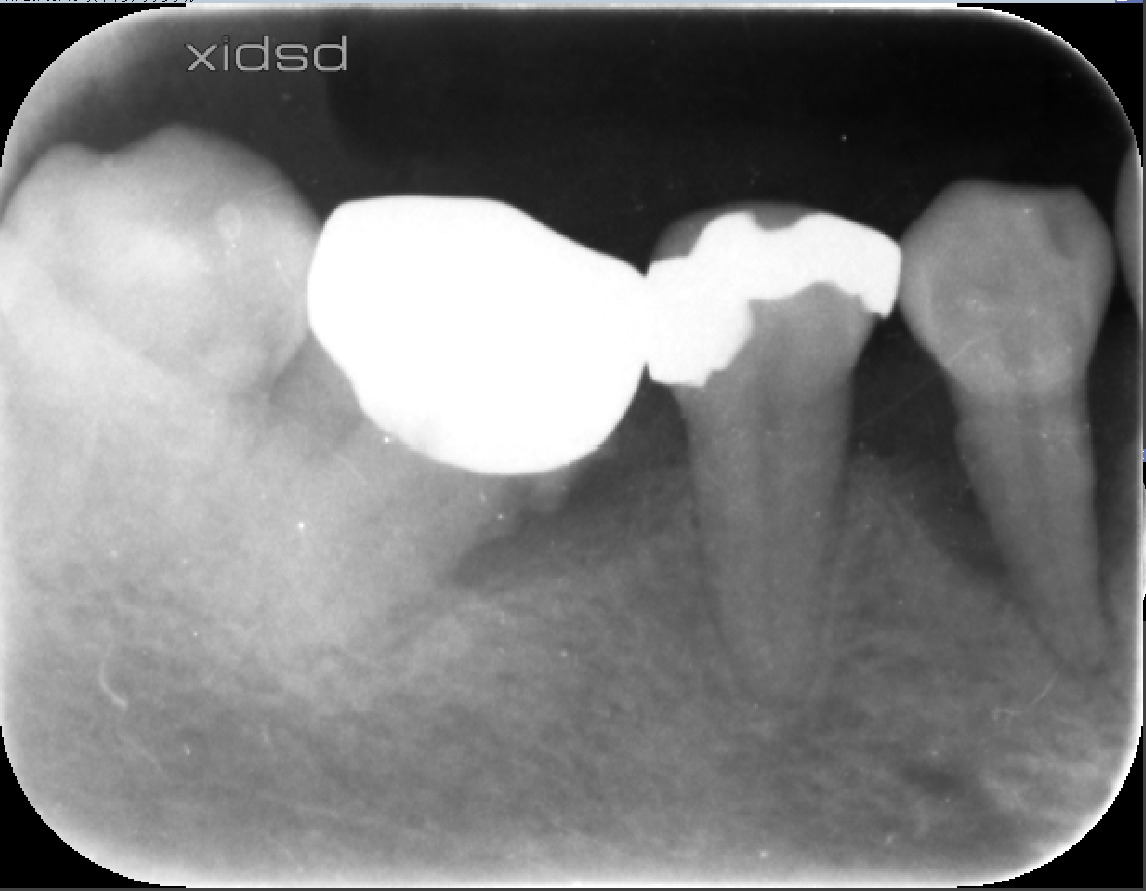

レントゲンを見ると

とくに右下4番(一番右の歯)が根の先まで骨が溶けています。歯周ポケットは8mm

徹底的な歯ブラシ指導の後MINSTの処置を行いました。